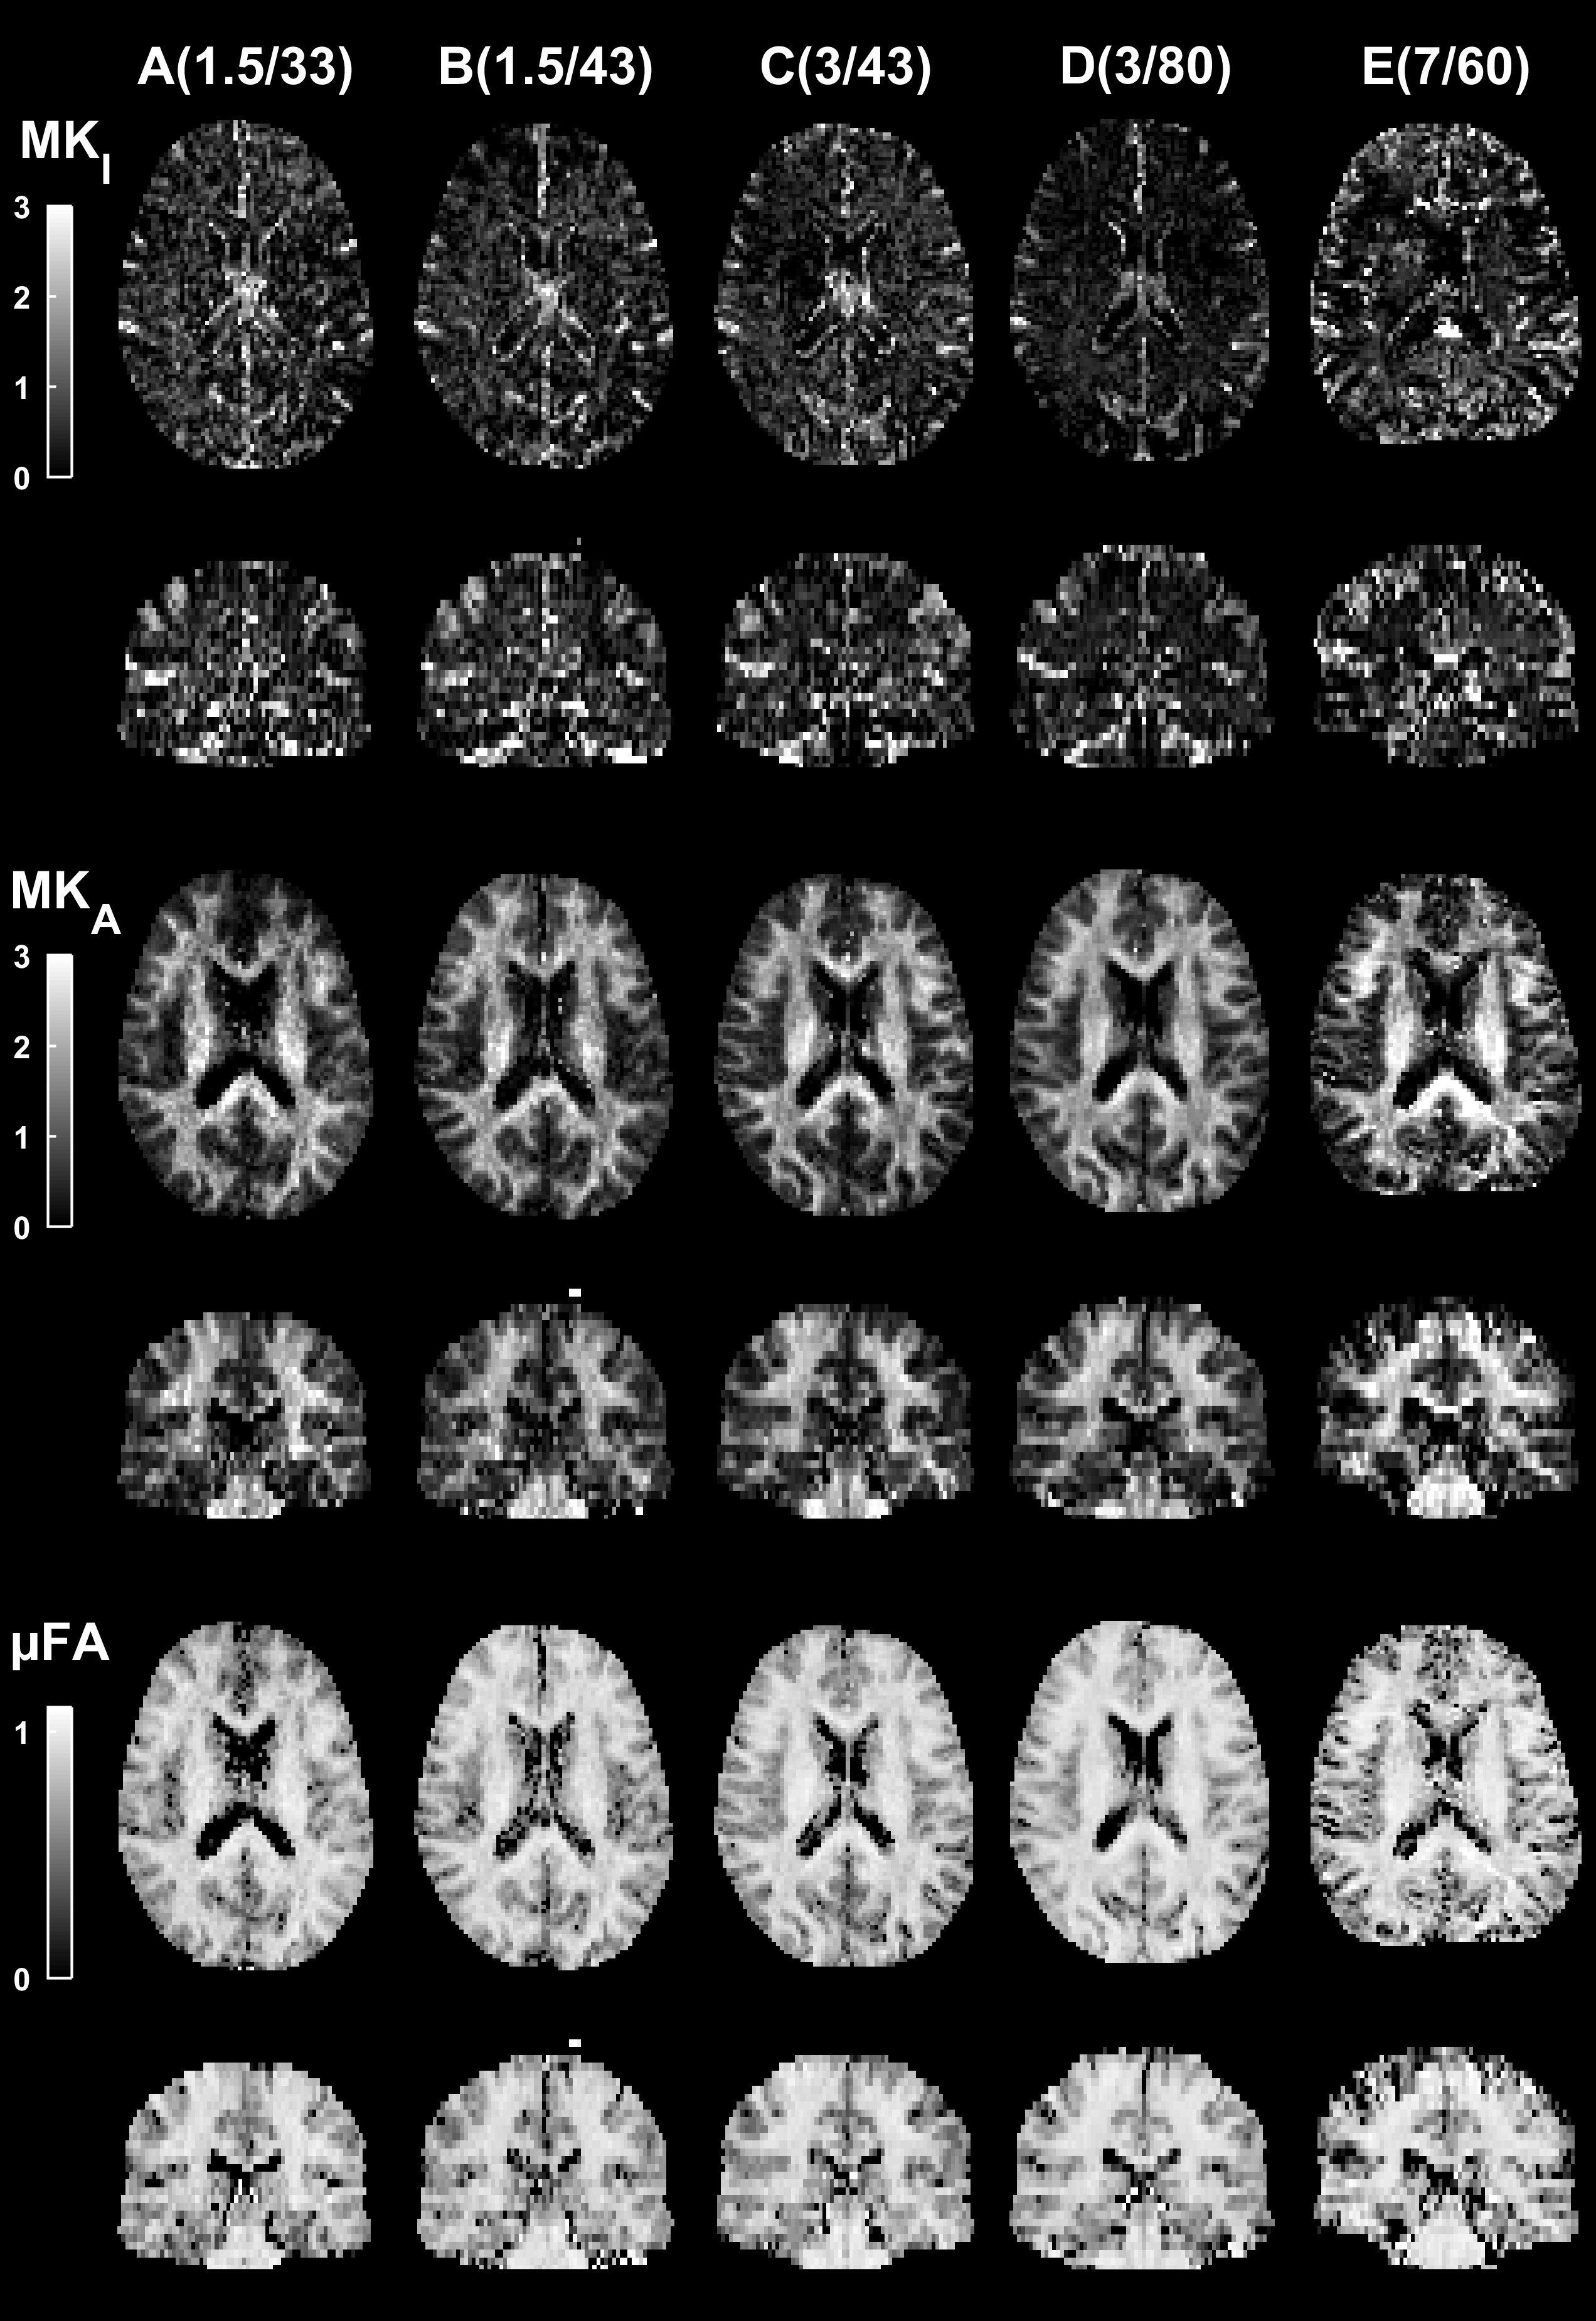

Tensor-valued diffusion encoding is an emerging technique within diffusion MRI. The novelty lies in the multidimensional encoding of the diffussion process. To support such encoding, we must replace the conventional diffusion encoding sequence with arbitrary gradient waveforms that facilitate a large range of encoding strategies. In doing so, we also need to store new kinds of experimental information to support traceability. In this project, we will extend the MRI pulse sequence to calculate and embed several necessary parameters in the DICOM header.